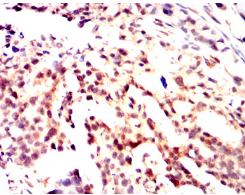

ID3 Mouse Monoclonal antibody[4C8D8]

IHC    1/200 - 1/1000